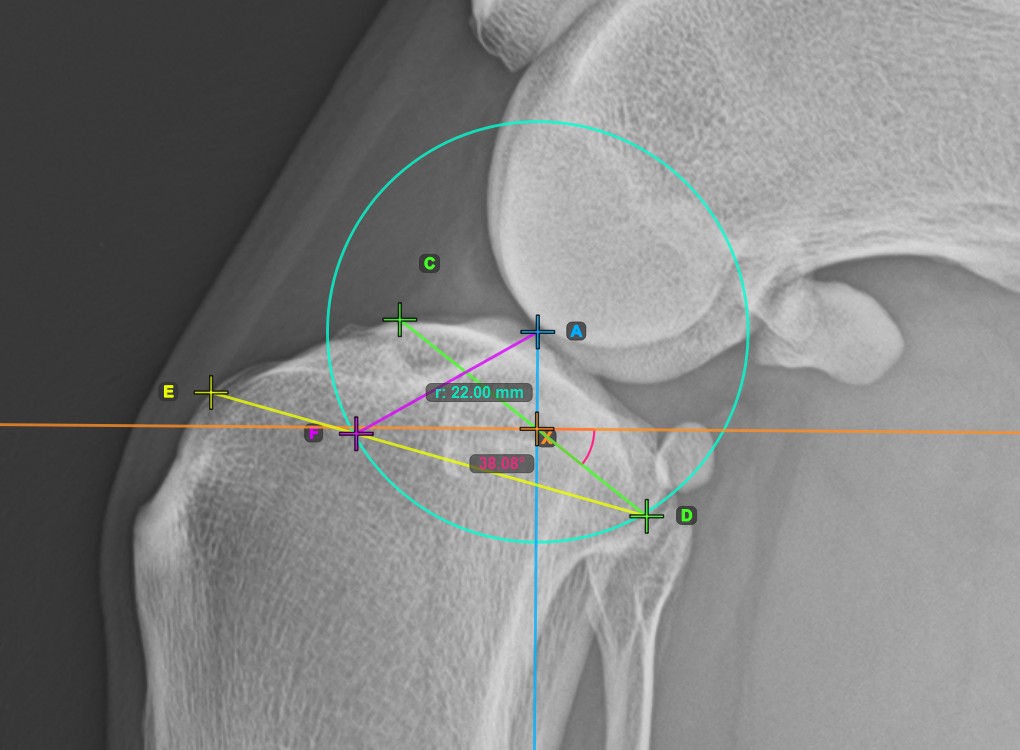

Complete the TPA Angle measurement by marking the most caudal point of the tibial head (tibial plateau). The TPA Angle is automatically calculated as the angle between the line connecting the two points on the tibial plateau and the perpendicular line to the long axis of the tibia.

The image below depicts the usual placement of the most caudal point on the tibial plateau and the automatically calculated TPA Angle measurement.